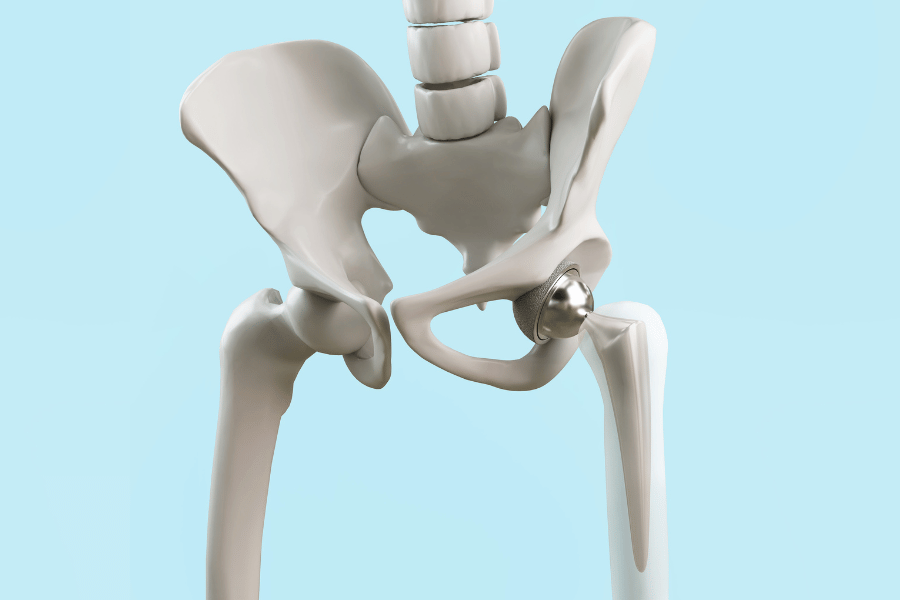

- Kolk

Kolki: nasveti in vaje za odpravljanje bolečin

Včasih so težave s kolki zelo očitne - bolečine so...

Poškodovan labrum kolka – kako ukrepati?

Do poškodbe labruma kolka običajno pride zaradi več razlogov. Glavni...Izpostavljeno